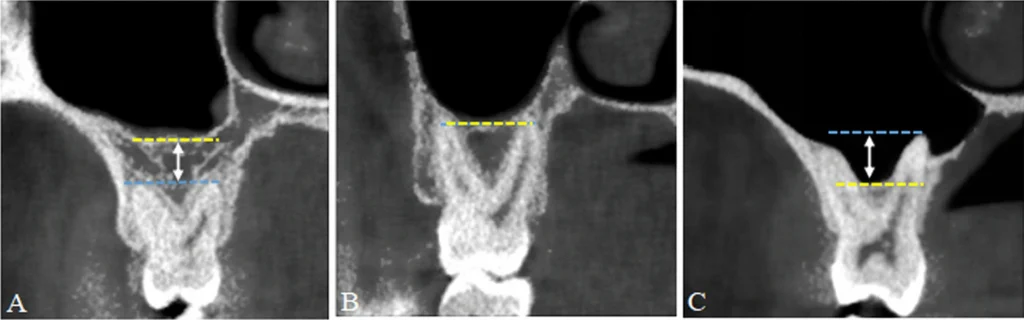

(Schematic diagram of classification of maxillary sinus pneumatization. A Type I normal pneumatization; B and C Type II extensive pneumatization. Yellow dashed line: horizontal line at the sinus floor; blue dashed line: horizontal line at the root apex; white double-headed arrow: distance between the sinus floor and the root apex. *)

When you lose teeth in the back of your upper jaw, the bone naturally begins to resorb (shrink). Simultaneously, the maxillary sinus—the air-filled cavity above your teeth—can expand downward. This process is known as Sinus Pneumatization.